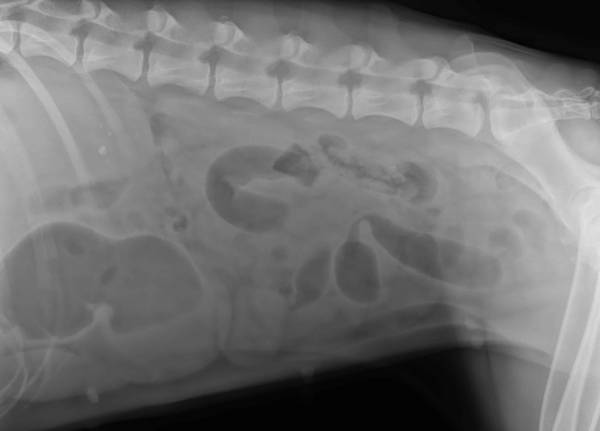

These are after lots of IV fluids and the passing of an hour and a half. What do you guys think/see?

I think I see gas bubbles; is her stomach trying to flip or ?? Scarey looking to me as I really don't know what I am looking at. Please share if you can, and I hope she is OK. Nan

The one x-ray that appears to be a top view shows an obvious enlargement on the ride side. It appears to me that there is some foreign matter going on. Stomach flip as Nan said...I can see that too.

I don´t know what kind of fluid they used, but normally the innards ( and the intestine ) should be visible much better (?). Did the fluid not go through the esophagus into the stomach?

3 vets at first hospital saw these, and the 1 vet I sent them to saw them. All saw obstructive pattern, albeit unclear as far as the nature of the obstruction. I'm extremely careful about what the dogs have access to, but Eden is a trouble-maker. She loves to grab something out of the hamper on her way out the backdoor through the laundry room. I find my son's clothes outside regularly- she's just sneaky enough to turn her head so we don't notice what she's got in her mouth. If any of mine are going to eat something stupid, it's Eden.

I posted these xrays because they were foolers.